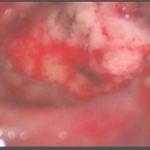

手術前1

術中写真

摘出 前

摘出 中

摘出 後